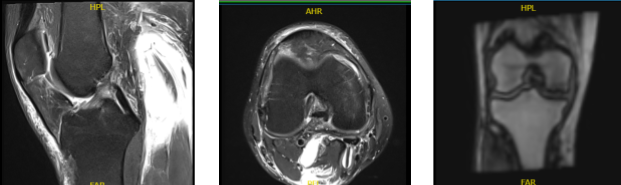

MRI Right Knee Non-contrast

Examination of the menisci reveals a tear of the posterior horn of the medial meniscus with abnormal signal within the posterior horn which contacts the inferior articular surface. No tears are seen within the lateral meniscus. The anterior and posterior cruciate and medial and lateral collateral ligaments appear intact.

The patellar and quadriceps tendons appear intact. There is a small joint effusion. The distal femur, proximal tibia and fibula, and patella appear intact without evidence of any fractures, contusions, or bony lesions. The popliteal fossa is clear. There is prepatellar and pretibial soft tissue edema.